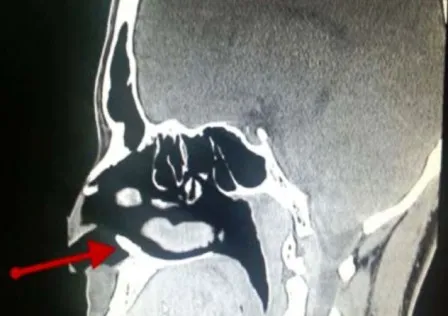

Trong suốt ban năm liền, người thanh niên 22 tuổi (được giấu tên) phải chịu ít nhất một lần máu mũi chảy bất thường mỗi tháng. Sau khi đi đến bệnh viện khám, các bác sĩ bất ngờ phát hiện một chiếc răng mọc bên trong lỗ mũi của anh.

Báo cáo nghiên cứu do Tạp chí “Case Reports” được xuất bản ở Mỹ cho biết, đây là một chiếc răng khôn, thay vì mọc trong miệng thì nó lại nổi lên ở lỗ mũi gây nên hiện tượng chảy máu mũi.

Theo tờ Live Science, các bác sĩ ở bệnh viện quân y King Fahd tại Dhahran, Ả-rập Xê-út đã rất ngạc nhiên khi phát hiện thấy chiếc răng lại mọc trong lỗ mũi. Sau khi gây mê và tiến hành ca tiểu phẩu, chiếc răng trong lỗ mũi đã được loại bỏ thành công.

Bác sĩ John Hellstein, một trong những tác giả của bài nghiên cứu, giải thích rằng mặc dù hiếm gặp nhưng những chiếc răng khôn có thể phát triển gần răng cửa và trong một số trường hợp những chiếc răng khôn này có thể phát triển thẳng đứng lên phía mũi.